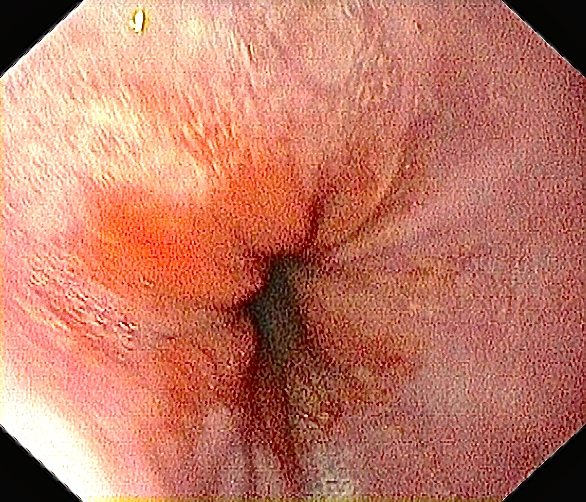

Slimhinnen i spiserøret mitt er nesten helt uten betennelse. Rosa, glatt og fint!